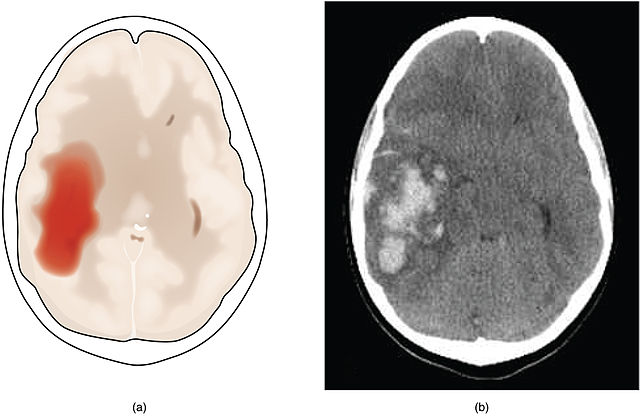

Identified patients are quickly registered (to get an MRN to facilitate the ordering of tests), the acute stroke team is notified, the ED places the ED Acute Stroke Order Set and the patient is taken directly to the CT suite. The Neurology team will meet the patient at the CT scanner and do their history and exam. The CT Head is primarily used to rule-out any intracerebral hemorrhage or other contra-indications for thrombolysis.